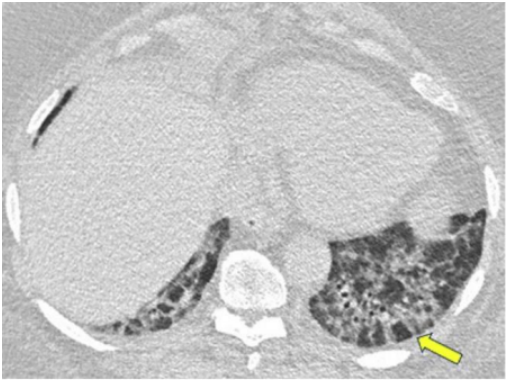

图源:Chest, 2022, 162(1):156-178.其他表现还包括小叶周围增厚和具有反晕外观特征的病变(环礁征)。图15所示为一名慢性持续性咳嗽和劳力性呼吸困难1年、体重减轻的32岁男性患者的CT图像,双侧中心磨玻璃样病灶完全被周围致密实变所包围,即反晕征或环礁征(A、B中红色箭头)。也存在不完全晕征(A、B中白色箭头)和小叶周围增厚(B中黄色箭头)。肺活检结果证实为OP。图源:Chest, 2022, 162(1):156-178.当以线性或网状为主的OP进一步发展,在周围实变或磨玻璃影后,基底和胸膜下网状形成,提示间质纤维化的发展。图16为一名73岁男性患者在呼吸困难发作4 d后获得的CT图像,分别在隆突水平(A,C)和以及肺基底水平(B,D)获得胸部CT图像。2019年的增强图像(A和B)显示双侧广泛的磨玻璃影;2021年的图像(C和D)显示磨玻璃影程度改善,但出现网状和牵拉性支气管扩张或细支气管扩张,这一模式与纤维化相符。右肺上、中、下叶的楔形活检结果显示OP。图源:Chest, 2022, 162(1):156-178.OP可导致广泛的双基底牵引性支气管扩张,其结果与非特异性间质性肺炎(NSIP)相似,并经常重叠。图17为51岁女性皮肌炎患者CT平扫图像,下肺基底图像显示双肺下叶实变,双侧胸膜下和磨玻璃影。矢状位图像上支气管明显扩张(B)。这些表现与OP和NSIP重叠一致。图源:Chest, 2022, 162(1):156-178.一名病态肥胖且进行性呼吸困难的67岁男性患者进行了CT扫描(图18)。肺基底部CT显示周围支气管壁增厚,伴有边界不清的磨玻璃密度和小叶周围增厚,特别是在左基底部(箭头),这些表现提示NSIP。外科肺活检结果与OP相符。